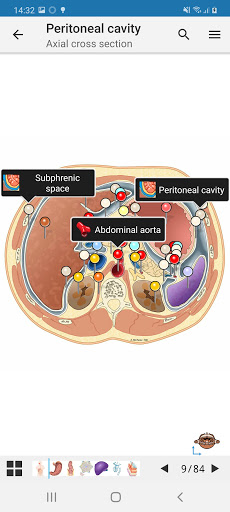

e-Anatomy tiene más de 26 000 imágenes que contienen series de imágenes en vistas axiales, coronales y sagitales, así como radiografías, angiografías, imágenes de disección, gráficos anatómicos e ilustraciones. Todas las imágenes médicas fueron etiquetadas cuidadosamente, más de 967 000 etiquetas disponibles en 12 idiomas, incluida la Terminologia Anatomica latina.

- Desplácese por los conjuntos de imágenes arrastrando el dedo

- Acerque y aleje el zoom

- Toque las etiquetas para mostrar las estructuras anatómicas

- Seleccione las etiquetas anatómicas por categoría